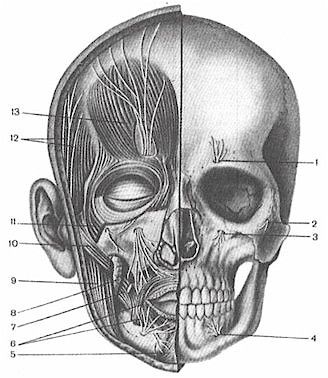

Анатомические изображения срединной сагиттальной линии черепа